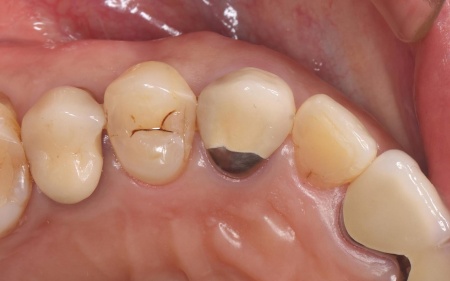

| 主訴 | 定期検診で通院中の患者様に「噛むと右上の犬歯に痛みがある」とご相談いただきました。 |

| 診断 | 拝見したところ、右上の犬歯には被せ物が装着されていました。 被せ物が装着されていると、レントゲン検査で歯の内部の状態を正確に確認することは困難です。 そこで、原因を詳しく調べるため被せ物を慎重に取り外し歯の内部を確認したところ、歯根が縦方向に割れる「歯根の垂直破折」が認められました。 また、このまま放置すると痛みや腫れが悪化し周囲の組織にも影響が及ぶ可能性があるため、抜歯が必要ですが、歯を抜いたままにすると隣の歯が動いて噛み合わせや歯並びに影響が出るおそれもあります。 以上のことから、抜歯したあとに歯を補う治療が必要と診断しました。 |

治療前